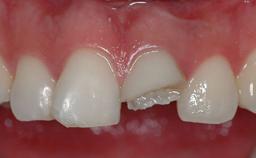

The patient presented with a failing tooth-supported fixed dental prosthesis with cantilever extension replacing the right maxillary central incisor. His chief presenting complaint was poor esthetics, in particular the dark discolored margin around the abutment tooth, the maxillary left central incisor. He reported a history of trauma at a young age, which necessitated the replacement of his maxillary right central incisor as well as root canal therapy of the adjacent left central incisor. The existing prosthesis had been in situ for over 20 years. The initial periapical radiograph displayed good proximal bone levels at the adjacent teeth and a wide incisive canal, which was a concern. The left central incisor presented a very wide root canal treatment with compromised radicular dentin thickness, which was a consideration in the decision between a new tooth-supported fixed dental prosthesis vs. an implant-supported prosthesis. After a lengthy discussion on the risks and benefits of both treatment options, the patient decided on a single-tooth implant replacement.